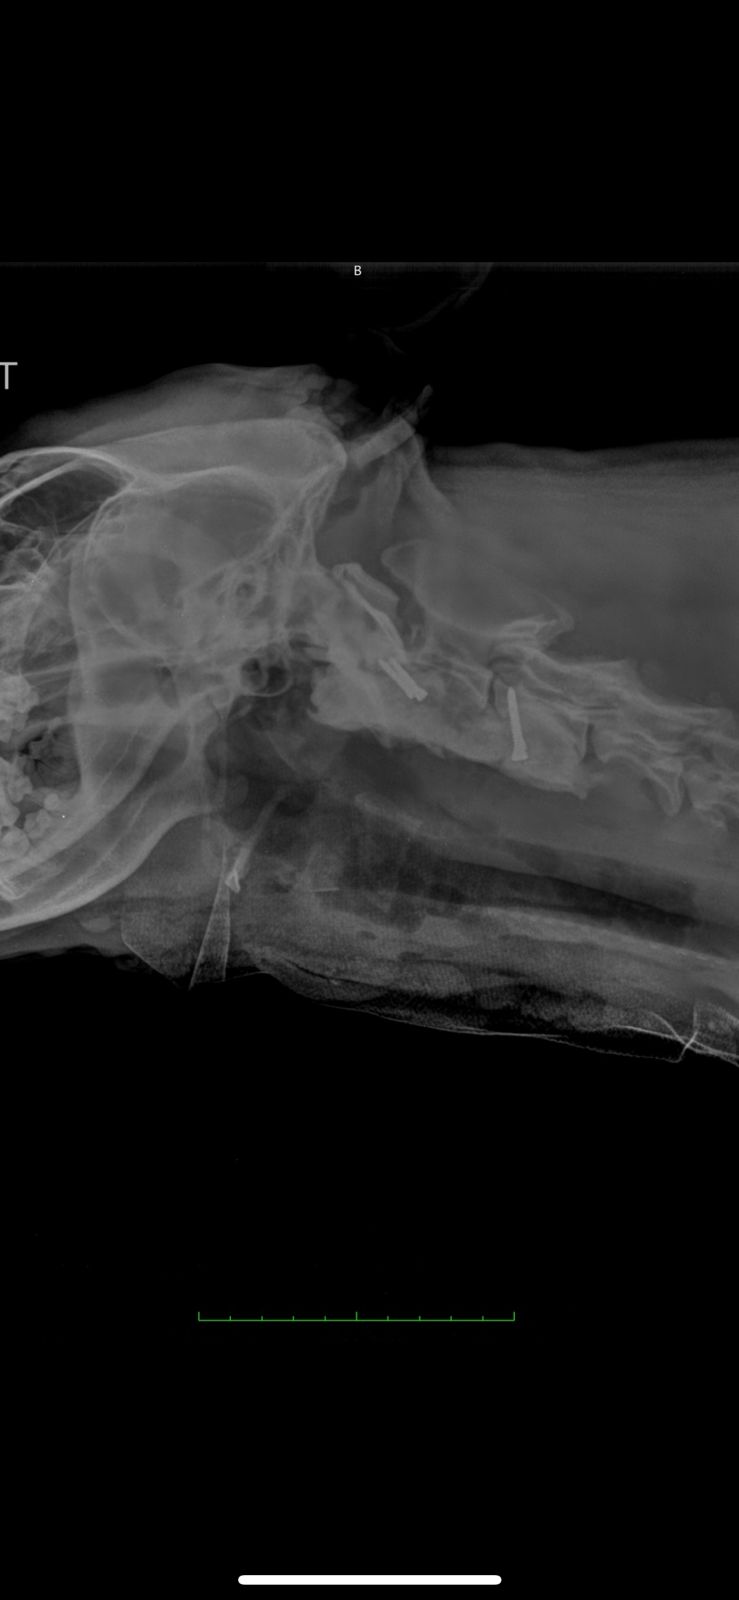

A thorough neurological examination followed by a CT scan revealed a C2 vertebral fracture with severe spinal cord compression along with a scapular fracture. Woody also experienced intense pain when flexing his neck. Given the risk of permanent damage, the surgical team decided to proceed with an advanced spinal fixation procedure using screws and PMMA.